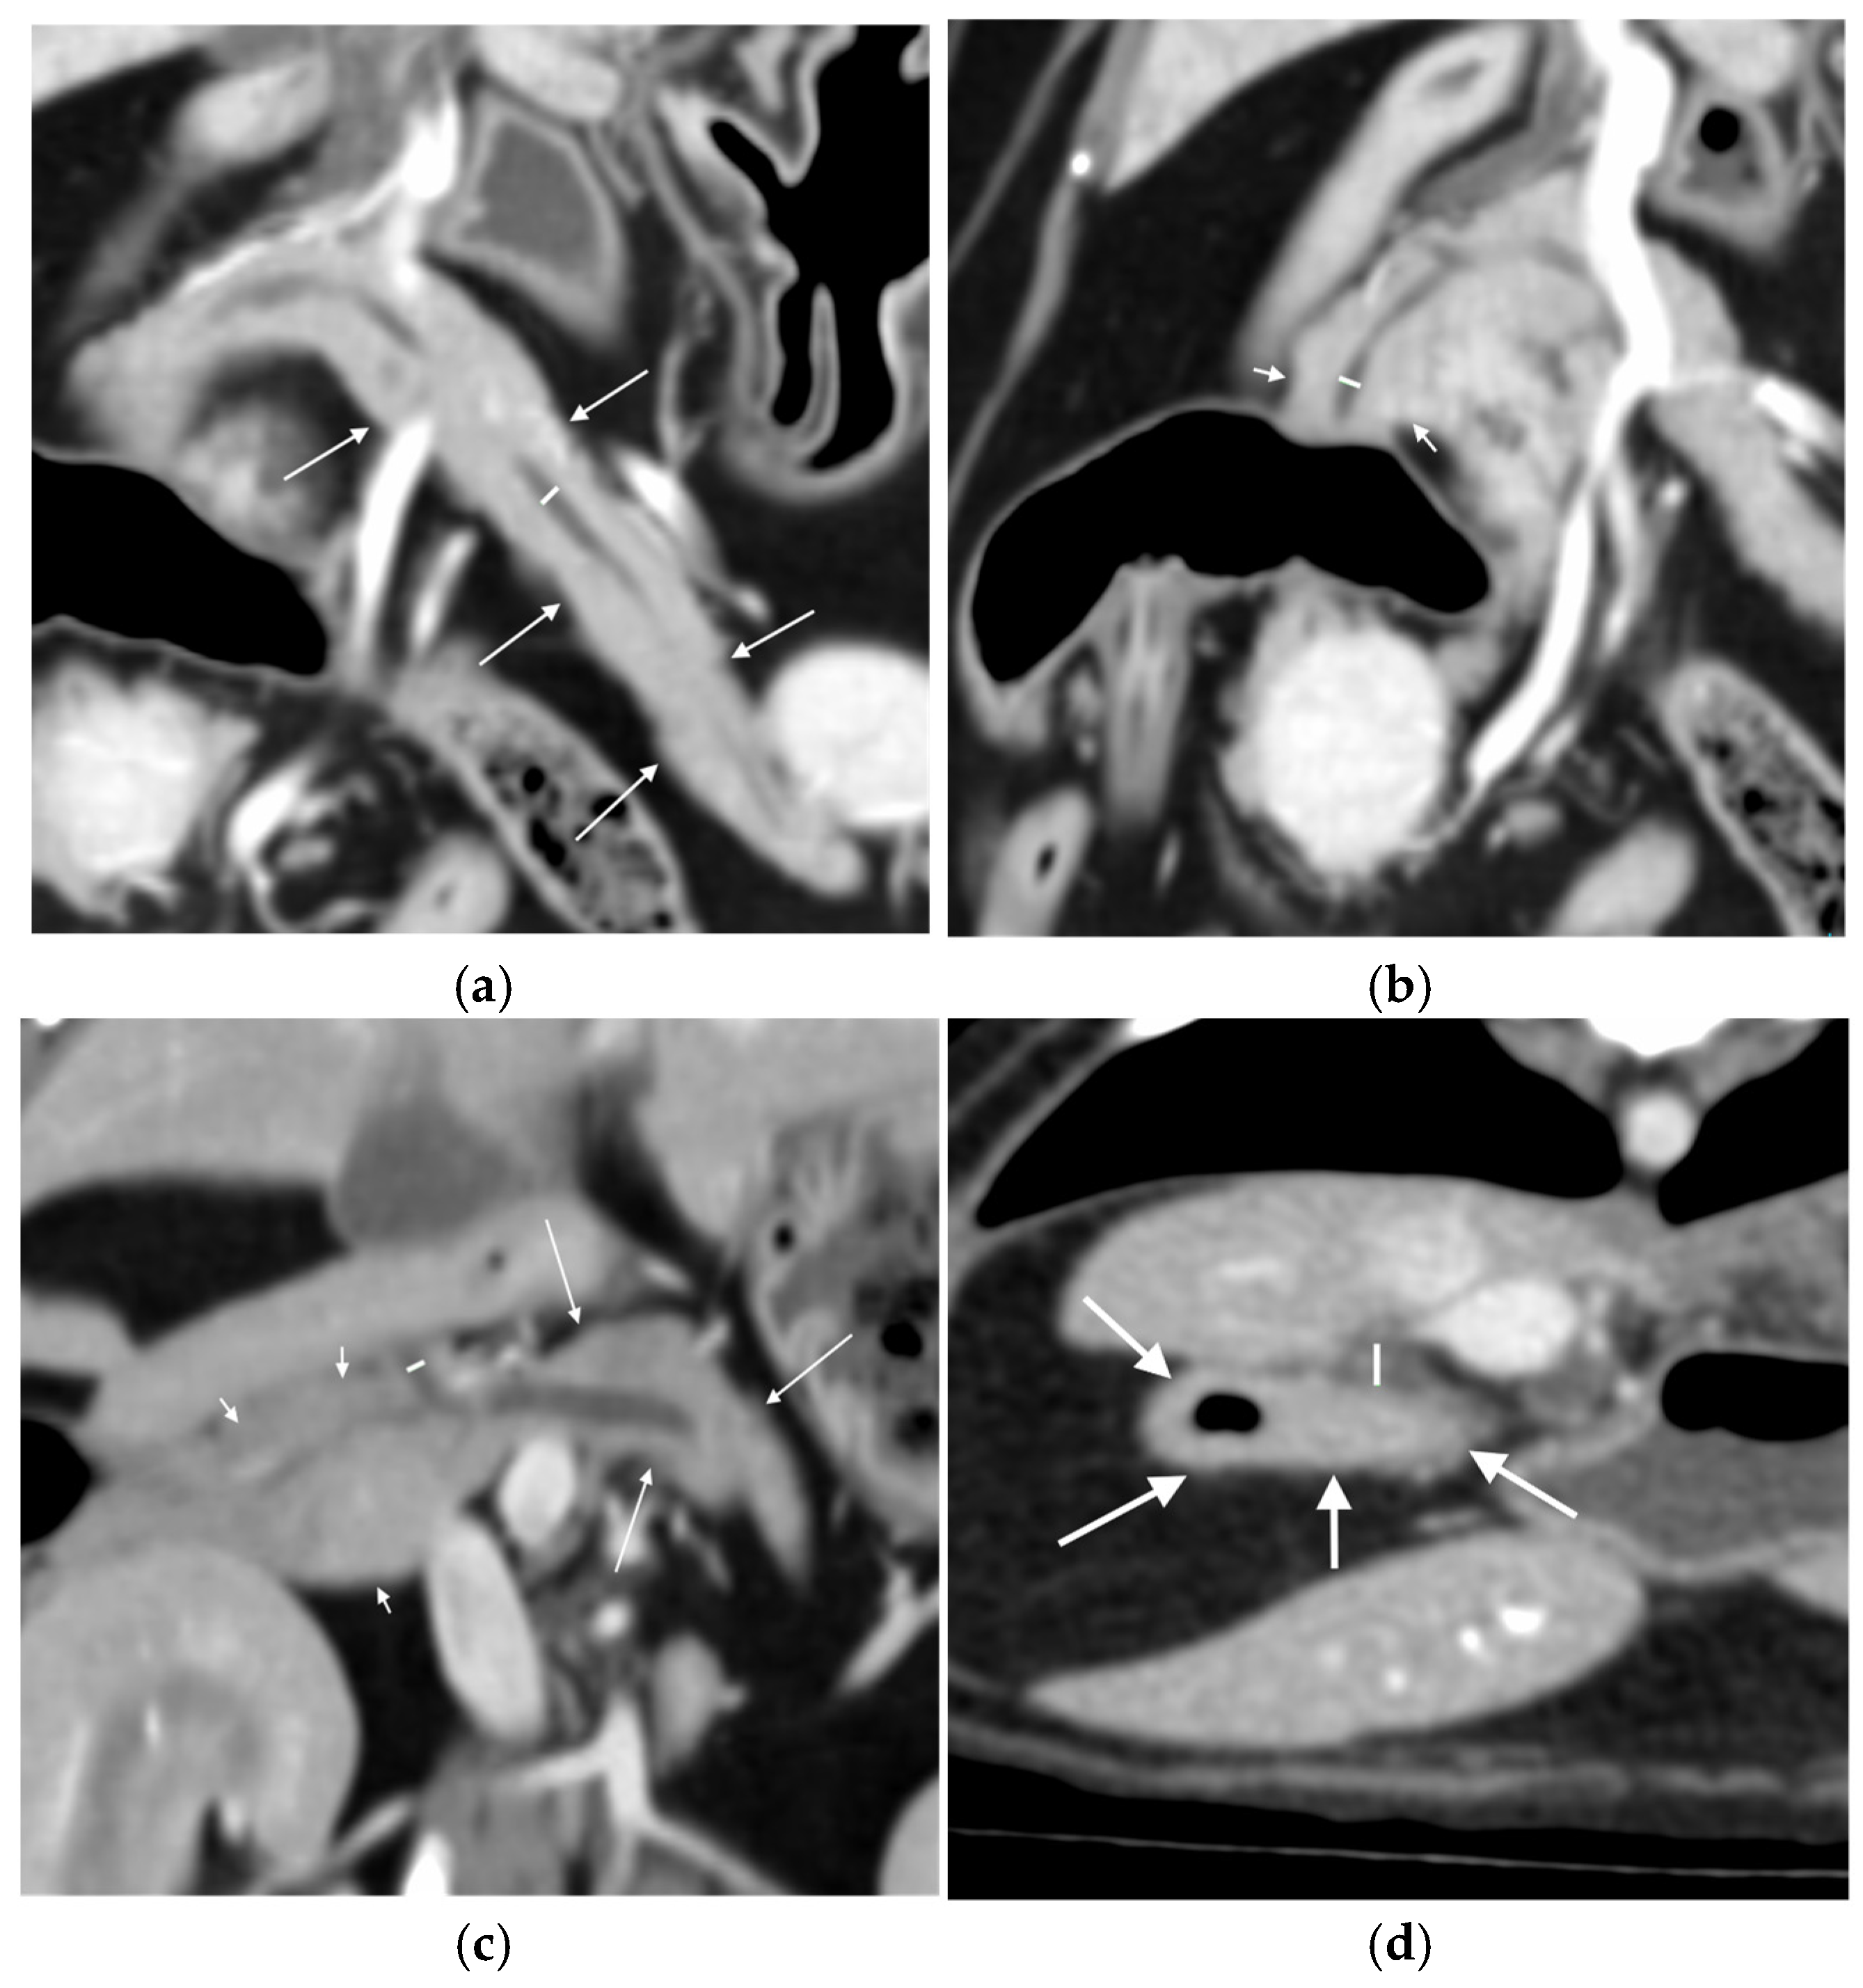

- Width from outer layer to outer layer, and Likert visibility scale pre and post-contrast, of the right pancreatic duct at its widest point on a dorsal plane reconstruction (Figure 1b).

- Width from outer layer to outer layer, and Likert visibility scale pre and post-contrast, of the common pancreatic duct as it exits the pancreatic parenchyma on a dorsal plane reconstruction (Figure 1c).

- Diameter of the duodenal papilla post-contrast taken perpendicular to the duodenal wall on the transverse image (Figure 1d).